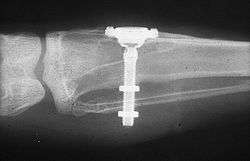

The design of implants, has to account for a lifetime of real-world use in a person's mouth. Regulators and the dental implant industry have created a series of tests to determine the long-term mechanical reliability of implants in a person's mouth where the implant is struck repeatedly with increasing forces (similar in magnitude to biting) until it fails.[16]